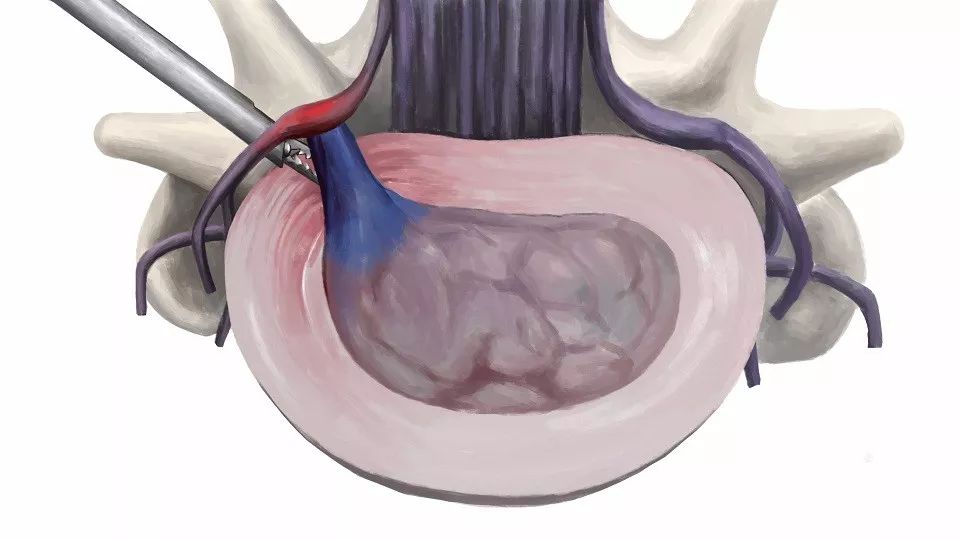

椎间孔镜技术属于脊柱内镜技术,近年来成熟应用于临床的尖端技术之一,秉承微创理念,脊柱稳定性影响较小。优点主要有:

1、微创:皮肤切口仅7mm;通过侧方入路到达目标区域,避免传统后路手术对椎管和神经的干扰;不咬除椎板,不破坏椎旁肌肉和韧带,对脊柱稳定性无影响。

3、安全性高:局部麻醉,患者术中全程清醒,术中能与患者互动,不伤及神经和血管;基本不出血,手术视野清晰,大大降低误操作的风险。

4、直接:直接切除突出间盘,手术减压明确。